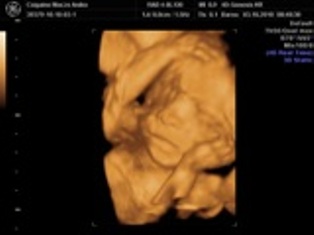

4D: a legtobb konyv azert az ellen van, hogy az anyuka az elso bevasarlokozponti 4Dszalonba beterjen kepeket csinaltatni, mintha pedikuroshoz menne... Mert azert annyira nem tutti, hogy egyaltalan nem art a babaknak (persze az orvosilag indokoltaknal tuttira nagyobb az elonyuk, mint a kockazatuk). Es tenyleg a terhesseg kozepetol az ikrek mar nehezen latszanak, ugyhogy koran erdemes elmenni, ha mar megy valaki. Ami helyet en nagyon tudok ajanlani, az az Istenhegyi genklinika. Ott kombinalt teszttel, mindennel egyutt csinalnak 4D-t is; kap az ember DVD-t is, kepeket is, es rendkivul alaposak es kedvesek az orvosok, es mindent nagyon-nagyon jol elmagyaraznak. Raszanjak az emberre rendesen az idot, nem az az erzesed, hogy na, mikor mesz mar es jon a kovetkezo. Egyszer kepzeljetek, olyan is volt, hogy amikor meghalt a magzatom (11. het korul), es elmentem vizsgalatra, nem is fogadtak el penzt erte... AMugyis arban is szerintem nagyon korrektek (Becsben mult heten 250 eurot kertek egy reszletes UH-ert; es semmi kepet vagy DVD-t nem adtak ;-(.). Es ha osszekombinalod a kombinalt teszttel vagy valamivel, nem tetted ki a babat felesleges plusz UH-nak.